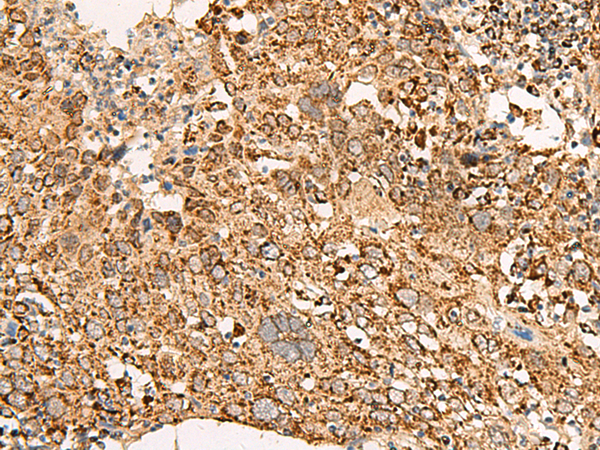

IHC positive control: |

Human cervical cancer and Human colorectal cancer |

IHC Recommend dilution: |

50-300 |